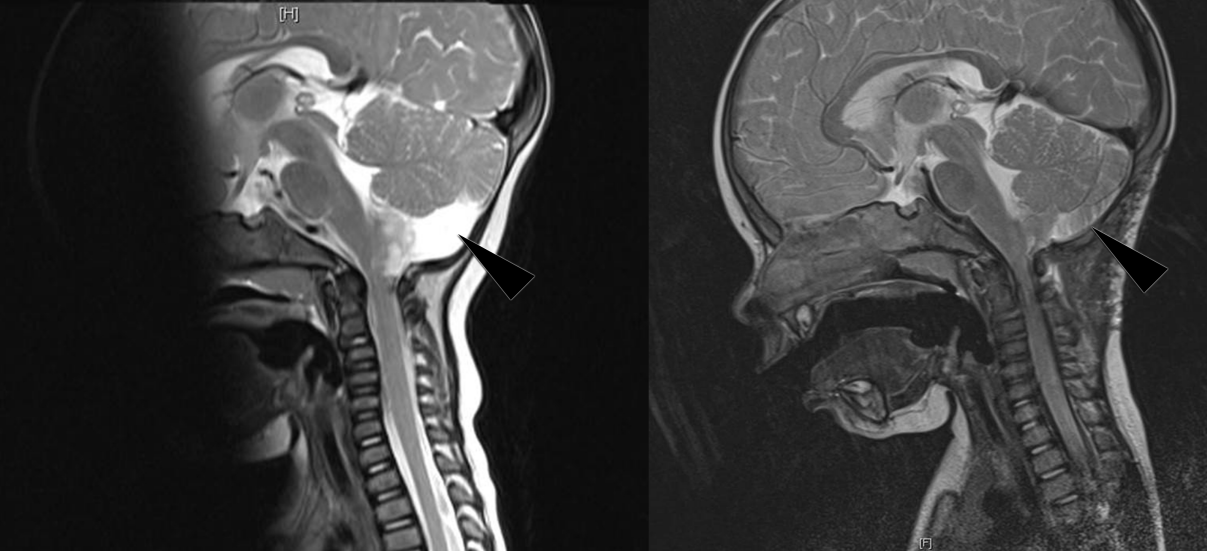

A magnetic resonance imaging (MRI) of the brain with and without gadolinium was performed. The MRI revealed a broad-based exophytic mass at the right posterolateral aspect of the medulla oblongata, obstructing the right foramen of Lushka and with a mass effect on the right cerebellar hemisphere (Figure 2 [Fig. 2]). Surgical resection of the tumor was performed (Figure 2 [Fig. 2]). Unfortunately, complete resection of the mass was impossible because of the risk of damaging adjacent structures. Histopathological examination on biopsy specimen revealed a pilocytic astrocytoma. No adjuvant chemotherapy or radiotherapy were given. Careful follow-up was done and post-operative physiotherapy was started. There was a good post-operative evolution with improvement of the right torticollis. At 6 and 42 months post-operatively, there was a residual torticollis of respectively 30° and 10° (Figure 1 [Fig. 1]). Photophobia was rated 7 and 2 on a scale of 10 respectively 6 and 42 months post-operatively.

Figure 2: MRI before and after resection